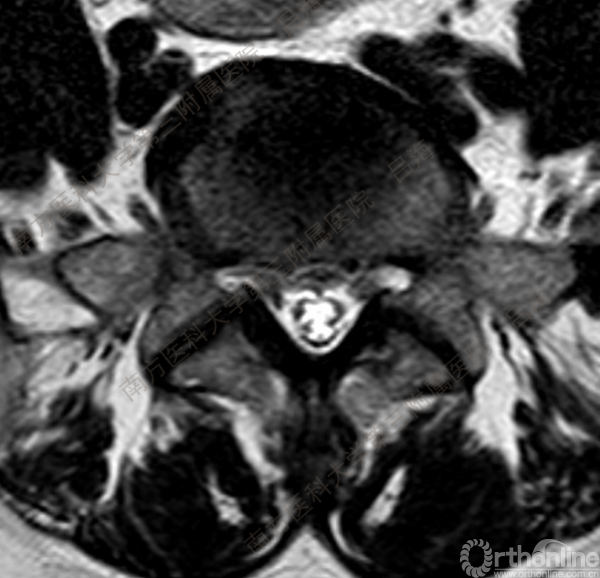

随着社会老龄化进程加快,胸腰椎退行性病变的治疗已经成为脊柱学术界的一个热点话题。MIS-TLIF手术可以治疗多种不同的胸腰椎退行性疾病,南方医科大学第三附属医院吕海教授结合病例为我们一一展示了该术式在治疗不同胸腰椎疾病时的具体手术过程。